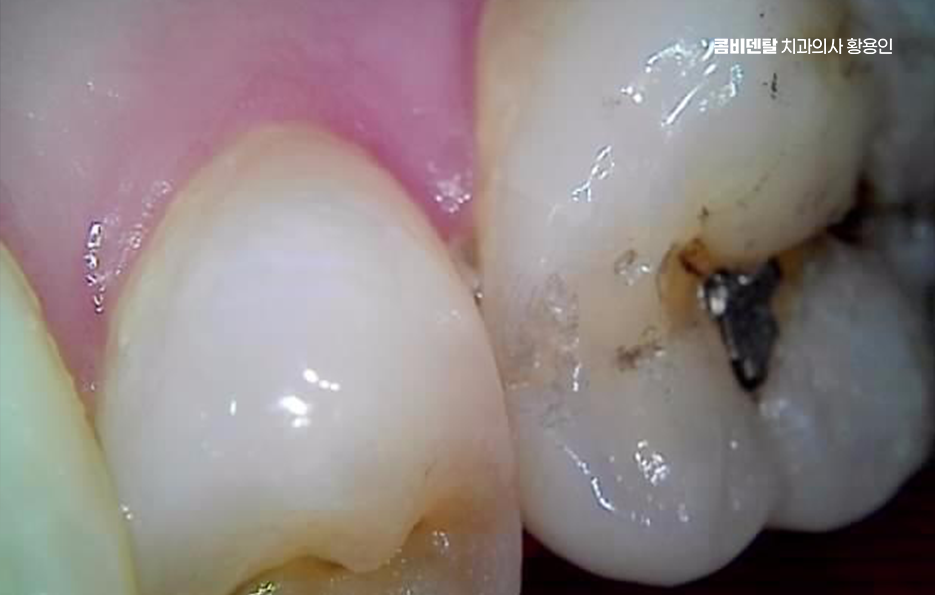

치아가 시린 흔한 원인은 상아질 노출로 치아는 가장 바깥쪽에 법랑질이라는 단단한 층이 있고, 그 안쪽에 상아질이 있는데 법랑질은 신경이 없지만, 상아질에는 미세한 관이 있어서 외부 자극이 내부 신경으로 전달되기 쉬우며 잇몸이 내려가거나 치아 목 부분이 닳으면 상아질이 드러나게 되는데 이때 차갑거나 단 음식이 닿으면 시린 증상이 나타날 수 있어요.

치아 시림 통증은 잇몸 질환도 원인 중 하나로 치주염이 진행되면 잇몸이 붓고 내려가면서 치아 뿌리가 노출되며 치아 뿌리는 법랑질로 덮여 있지 않아서 자극에 더 민감하고, 시린 증상이 반복되기 쉬우며 이 경우 염증을 먼저 치료해야 할 필요가 있어요

치아에 금이 간 경우에도 치아 시림 통증이 나타날 수 있는데 겉으로는 잘 보이지 않는 미세 균열이 있어도, 씹을 때마다 자극이 전달되면서 통증이 생길 수 있으며 특히 특정 방향으로 씹을 때 찌릿한 통증이 반복된다면 크랙을 의심해볼 수 있어요.